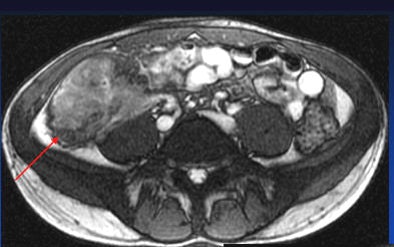

MRI results were then compared to colonoscopy and pathology reports to determine the presence or absence of disease in evaluable bowel segments. Individual imaging parameters (including wall thickening, enhancement, T2 signal, mesenteric vascular prominence, and adenopathy) were also separately analyzed to determine their independent predictive value, the authors wrote.

The study team acquired steady-state free-precession (SSFP) images of the abdomen and pelvis (TR= 4 ms, TE = 2 ms, slice thickness 8 mm for coronal images and 8-mm for axial images). Axial and coronal fat-suppressed half-fourier single-shot fast-spin echo (SSFSE) and axial spoiled-gradient images were also obtained through the abdomen, followed by T1-weighted fat-suppressed spoiled-gradient echo (LAVA/VIBE) images, before the injection of 1 mmol/kg of gadopentate dimeglumine contrast (Bayer Healthcare) followed by a saline flush and postcontrast imaging.

A single experienced abdominal radiologist, blinded to the final results, interpreted all of the MRE images, rating wall thickness, abnormal enhancement, abnormal T2 signal, and mesenteric vascular prominence on a scale of 1-4. All endoscopy reports were reviewed for mention of inflammatory changes in specific bowel segments, and pathology reports were reviewed for the presence of inflammatory disease, the study team reported.

Interestingly, the results were in line with smaller studies that used antiperistaltic agents, they wrote. As in those studies, MRE showed its real strength in a couple of features of active Crohn's disease. "Analysis of individual MR parameters demonstrates that wall thickening and abnormal enhancement are the most sensitive indicators of Crohn's disease on MRE while abnormal T2 signal, mesenteric vascular engorgement, and adenopathy were insensitive but specific," he wrote.